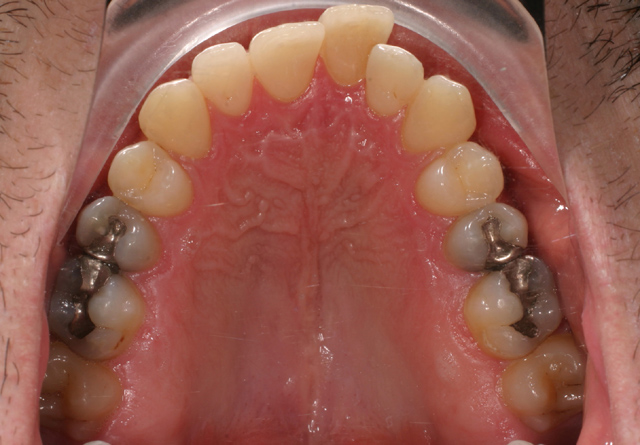

Il soggetto di sesso maschile si è presentato alla nostra osservazione per la correzione dell'affollamento dentario.

Trattamento: Estrazione di 1.5 e 2.5 superiormente con ancoraggio con un bottone di Nance

Estrazioni inferiori di 3.4 e 4.4 con arco linguale

Tecnica MBT con chiusura degli spazi per arretramento in massa.

Finitura e contenzione con essix superiore e retainer inferiore.